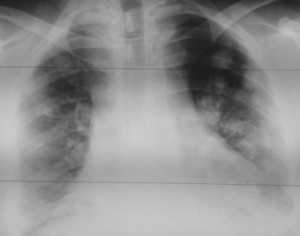

![image007]()

Как выглядят метастазы в легких на рентгене? Слева — узловые образования у пациента с раком яичка. Справа - метастазы рака яичников гематогенного характера с выраженным опухолевым лимфангиитом (обратите внимание на деформированный сетчатый, линейный характер легочного рисунка).